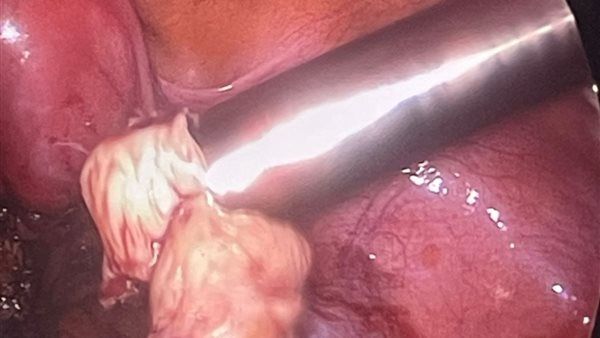

ومن جانبها، أوضحت الدكتورة أسماء مصطفى رشاد رئيس قسم النساء والتوليد، أنه تم إجراء عملية استئصال كلي للرحم وقناتي فالوب باستخدام المنظار البطني لمريضة تبلغ من العمر 45 عامًا، كانت تعاني من نزيف رحمي نتيجة أورام ليفية متعددة، وقد تمت العملية بنجاح بمشاركة الدكتور أحمد عبداللطيف الباز استشاري النساء والتوليد، والدكتورة سمر عبدالرؤوف طبيب مقيم زمالة النساء والتوليد.

كما أوضح الدكتور عبدالله صلاح الدين أخصائي النساء والتوليد، أنه تم إجراء عملية استئصال ورم ليفي بالجدار الخلفي للرحم بحجم 6×6 سم باستخدام المنظار الجراحي، مع فك التصاقات شديدة بقناة فالوب اليسرى والتعامل مع التصاق المبيض بجدار البطن، وذلك بمشاركة الدكتورة أسماء مصطفى رشاد والدكتورة سمر عبدالرؤوف.

وأضاف أنه تم أيضًا إجراء عملية دقيقة لاستئصال كلي للرحم والمبيضين لسيدة تبلغ من العمر 55 عامًا، تعاني من ارتفاع ضغط الدم وارتخاء بالصمام الميترالي، مع وجود نزيف مهبلي وآلام شديدة بالحوض نتيجة ورم ليفي كبير بحجم 10×15 سم، حيث تم استئصال الرحم وعنق الرحم والمبيضين والورم الليفي بنجاح، بمشاركة الفريق الطبي ذاته، وبالتعاون مع فريق التخدير بقيادة الدكتور جهاد محمد، وفني التخدير الأستاذة نادية، وهيئة التمريض التي ضمت: بسمة وعزة، وتحت إشراف مشرف العمليات مستر محمد رضا.